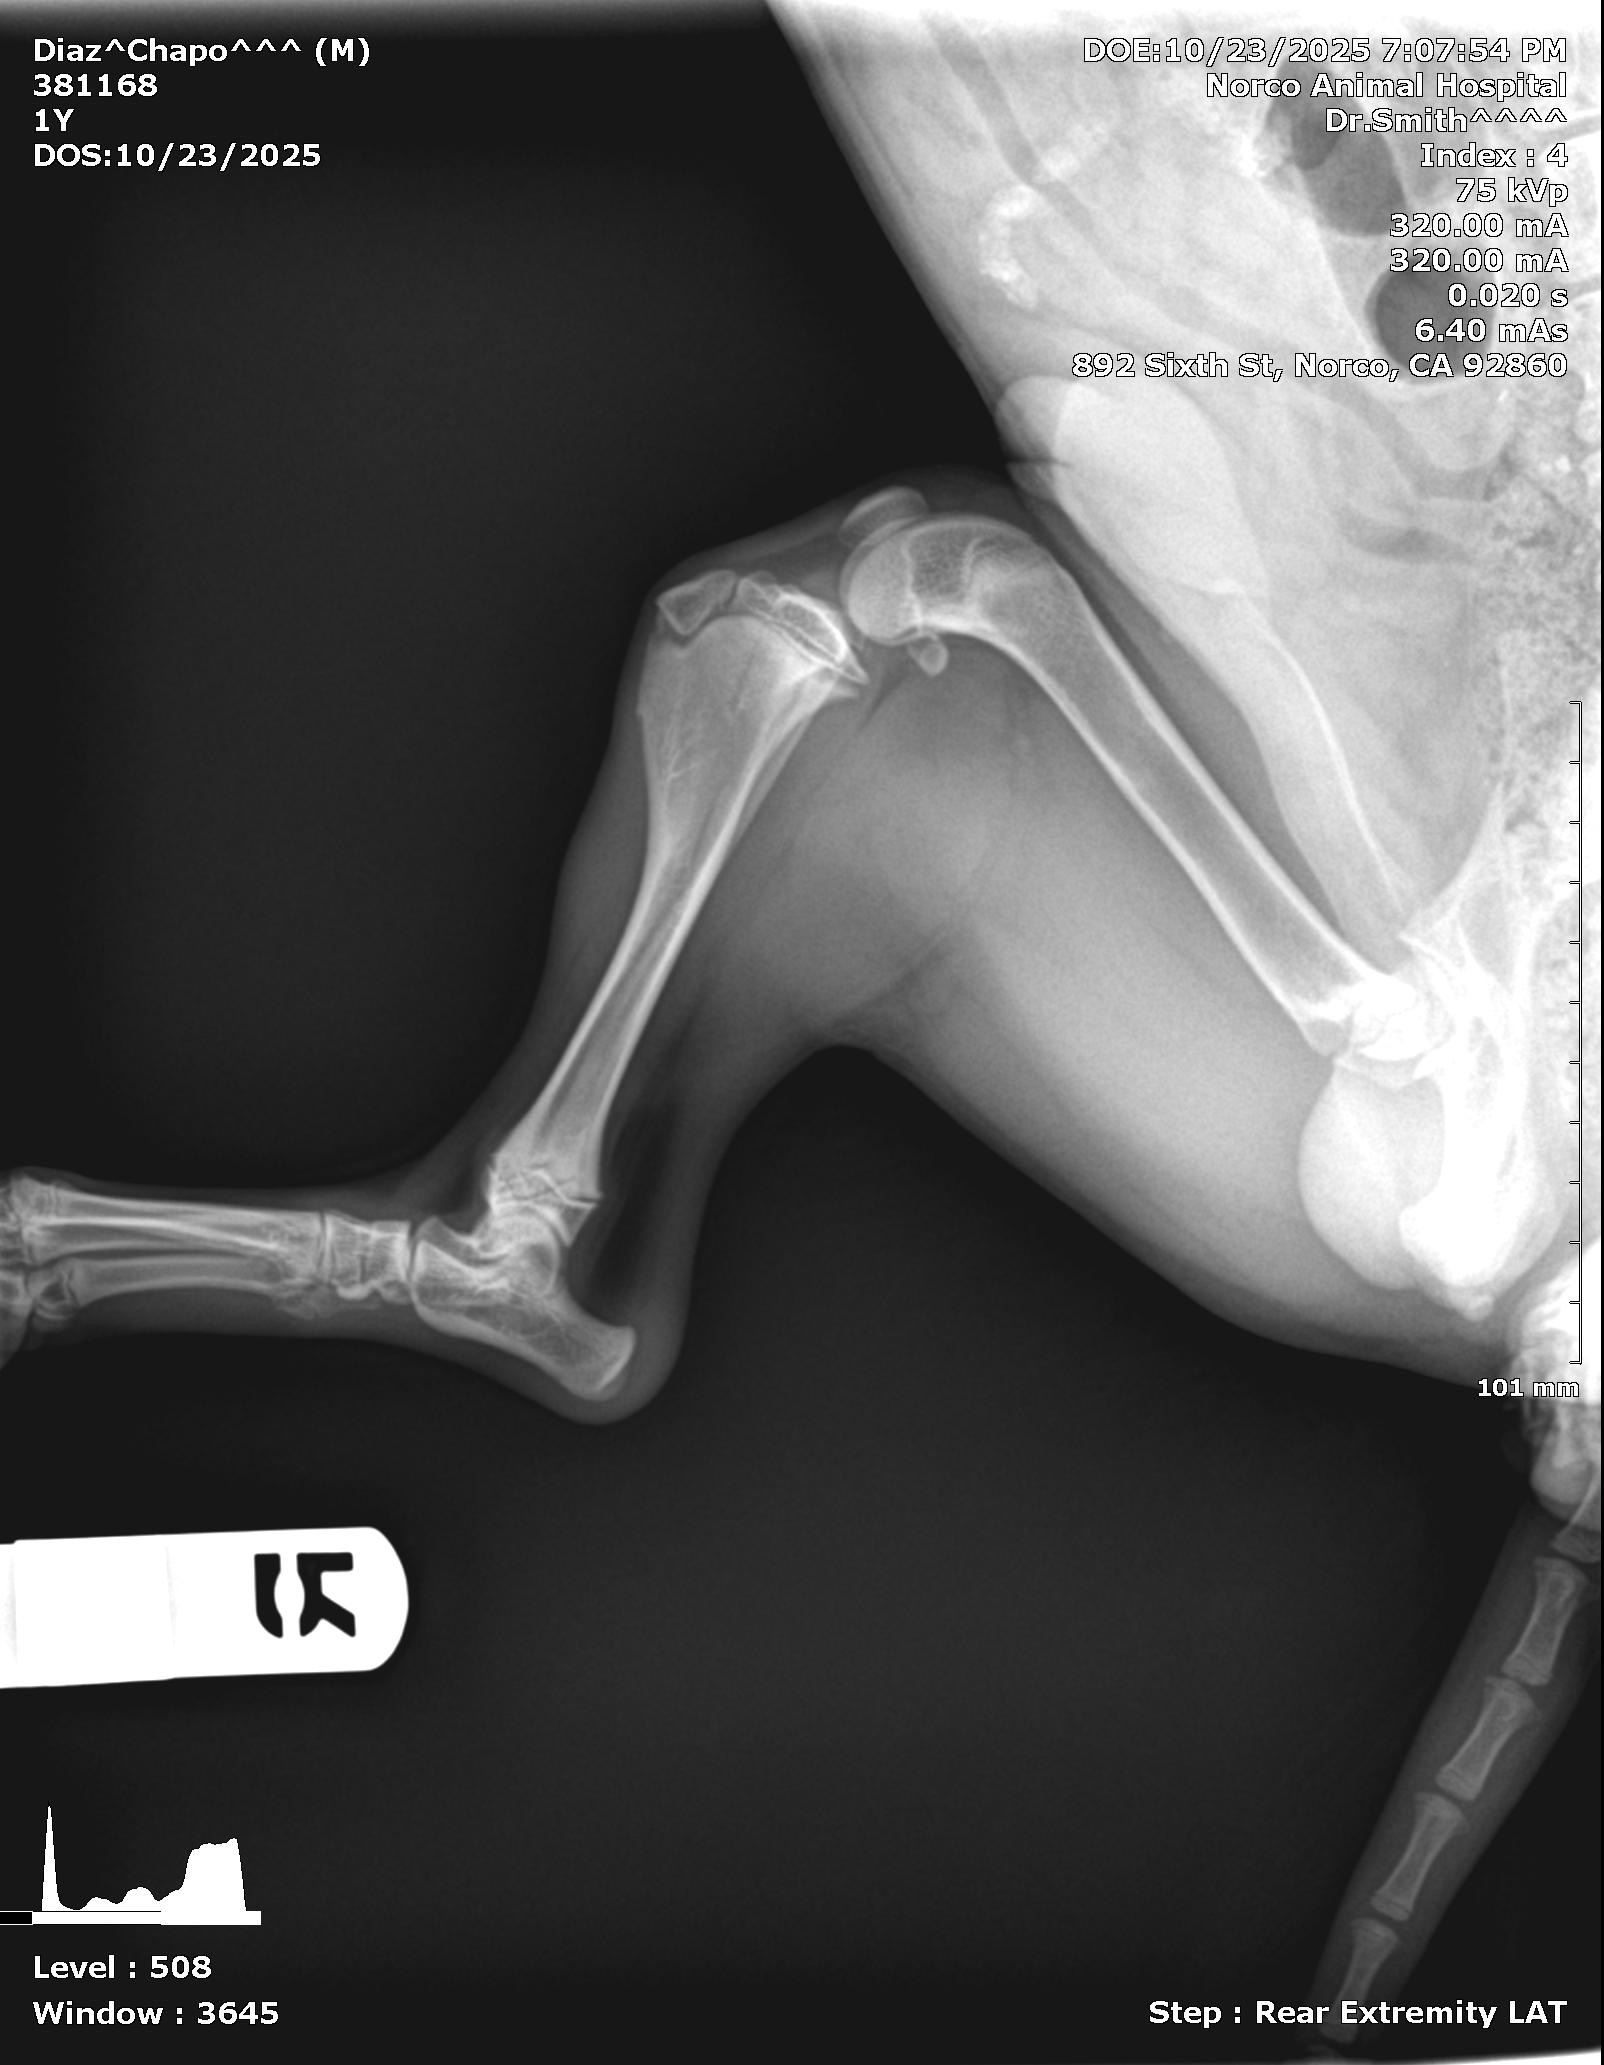

Chapo was abandoned by his previous owner. The owner had 4 puppies in total and gave them all to a mutual friend of mine so she gave chapo to me. He’s almost 1 year old yesterday he was on the leash but managed to run off and got ran over we did go to the vet and got test done I did use a credit card but he has a fractured leg which I can’t afford the surgery if you all could help with anything or even pray for us it would mean the world to me, thank you!